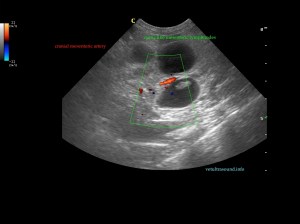

Findings: The ultrasound exam revealed a marked distention of a segment of the small intestine which ended in a narrowed lumen due to a thickened wall. The mesenteric lymph nodes were markendly enlarged and hypoechoic. A fine needle aspirate was performed.

After we decided the path of the needle, the insertion site was prepared with the Hibitane scrub and alcohol. Then we applied some gel on the Linear probe and covered with the elastic glove. Then the syringe was loaded with 5ml of air and attached to the needle. We performed techniques with and without aspiration depending on the blood that sometimes was withdrawn. The diagnosis was Lymphoma.

The GIF shows the frames from the normal small intestinal layering to the thickened abnormal wall in a perpendicular view.